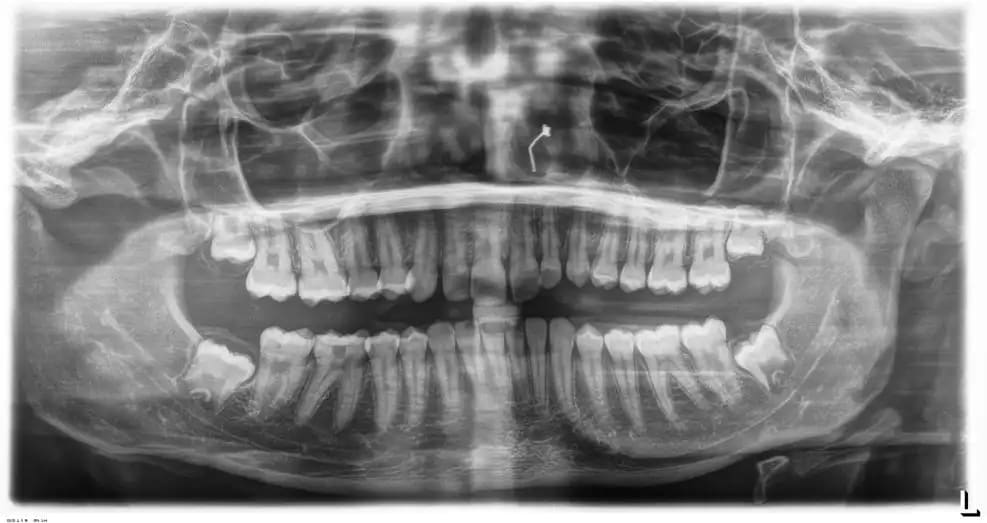

Et pour ceux qui me demandaient la pano de l'année précédente, exactement 1 an et 3 mois précédemment, la voici.

Vous pourrez comparer l'évolution rapide de la tumeur bénigne qui a refoulé les structures en les soufflant.

01/10/2025 à 07h31

Même l’edification radiculaire des dents de sagesse en l’espace d’une année est surprenante 🤔

Moi ce qui m'impressionne c'est le déplacement de la 38.